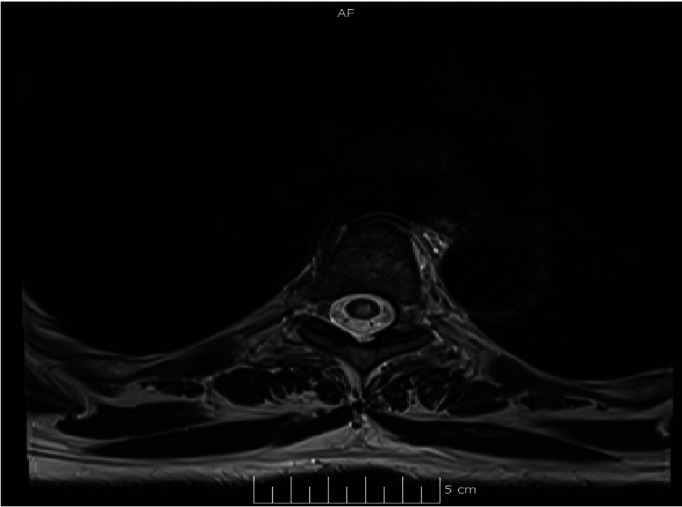

Abstract Image